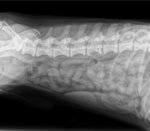

У собак 7 шейных, 13 грудных, 7 поясничных и 3 крестцовых позвонка. Межпозвоночные диски выполняют роль амортизаторов, снижая нагрузку на позвоночник. С возрастом диски теряют эластичность, становятся жёсткими и хуже распределяют нагрузки. При регулярных нагрузках они сжимаются и расширяются, что может привести к разрыву. Это вызывает сильную боль, повреждение нервов и даже паралич. В зависимости от расположения повреждённого диска, страдает определённая область тела — от шеи до задних конечностей.

При обращении в ветеринарную клинику проводится полное неврологическое обследование, которое помогает определить местоположение повреждённого диска и выявить другие болезни спины у такс. В обследование входят МРТ и рентгенография, позволяющие обнаружить возможные причины проблем с позвоночником, такие как переломы или опухоли. Для исключения рака и инфекционных заболеваний может быть выполнена спинномозговая пункция.

Вытянутое тело таксы характеризуется длинным позвоночником, состоящим из небольших позвонков. Между ними расположены овальные диски — мягкие, но упругие, которые позволяют позвоночнику сгибаться и разгибаться.

Каждый диск имеет плотную оболочку, удерживающую его на месте. Иногда оболочка не справляется, и диск начинает выползать. В позвоночном канале рядом с дисками находится спинной мозг — пучок нервных волокон, выполняющих функцию проводников.

Когда диск давит на нервные волокна, передача сигналов нарушается, что приводит к симптомам. Основной причиной сжатия спинного мозга диском является специфическое строение тела таксы — длинный позвоночник при коротких лапах создает большую нагрузку на позвоночник.